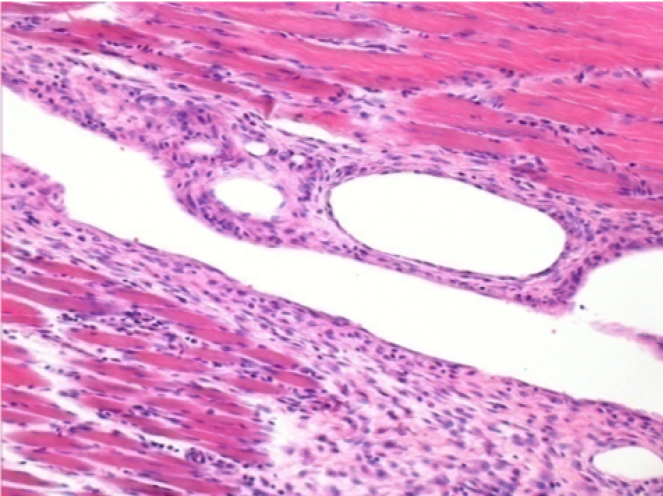

1 mese dopo Iniezione Endopeel

Scatola Nr 3

1 mese dopo Iniezione 0.1ml di Endopeel nel muscolo pretibiale destro ( Dx) .

Che cosa viene visualizzato in nero nella figura Sx : 100x-Giorno30 non é una necrosi come potrebbe immaginare un dilettante.

In effetti, 4 conclusioni devono essere prese in considerazione

- un artefatto di colorazione

- un`assenza di necrosi

- un`apoptosi

- un processo biorigenerativo

Sx : Controllo-100x-Giorno30

Dx:100x-Giorno30

Dx :400x-Giorno30